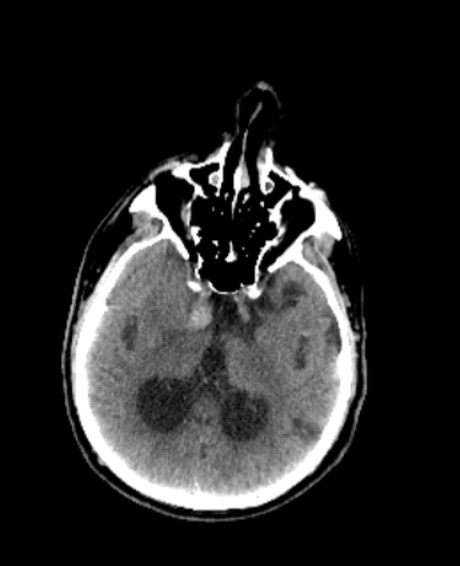

Method: The CT found the haemorrhage in right parahippocampal gyrus area. The MRI found signs of triventricular hydrocephalia.

Right parahyppocampal gyrus haemorrhage on CT